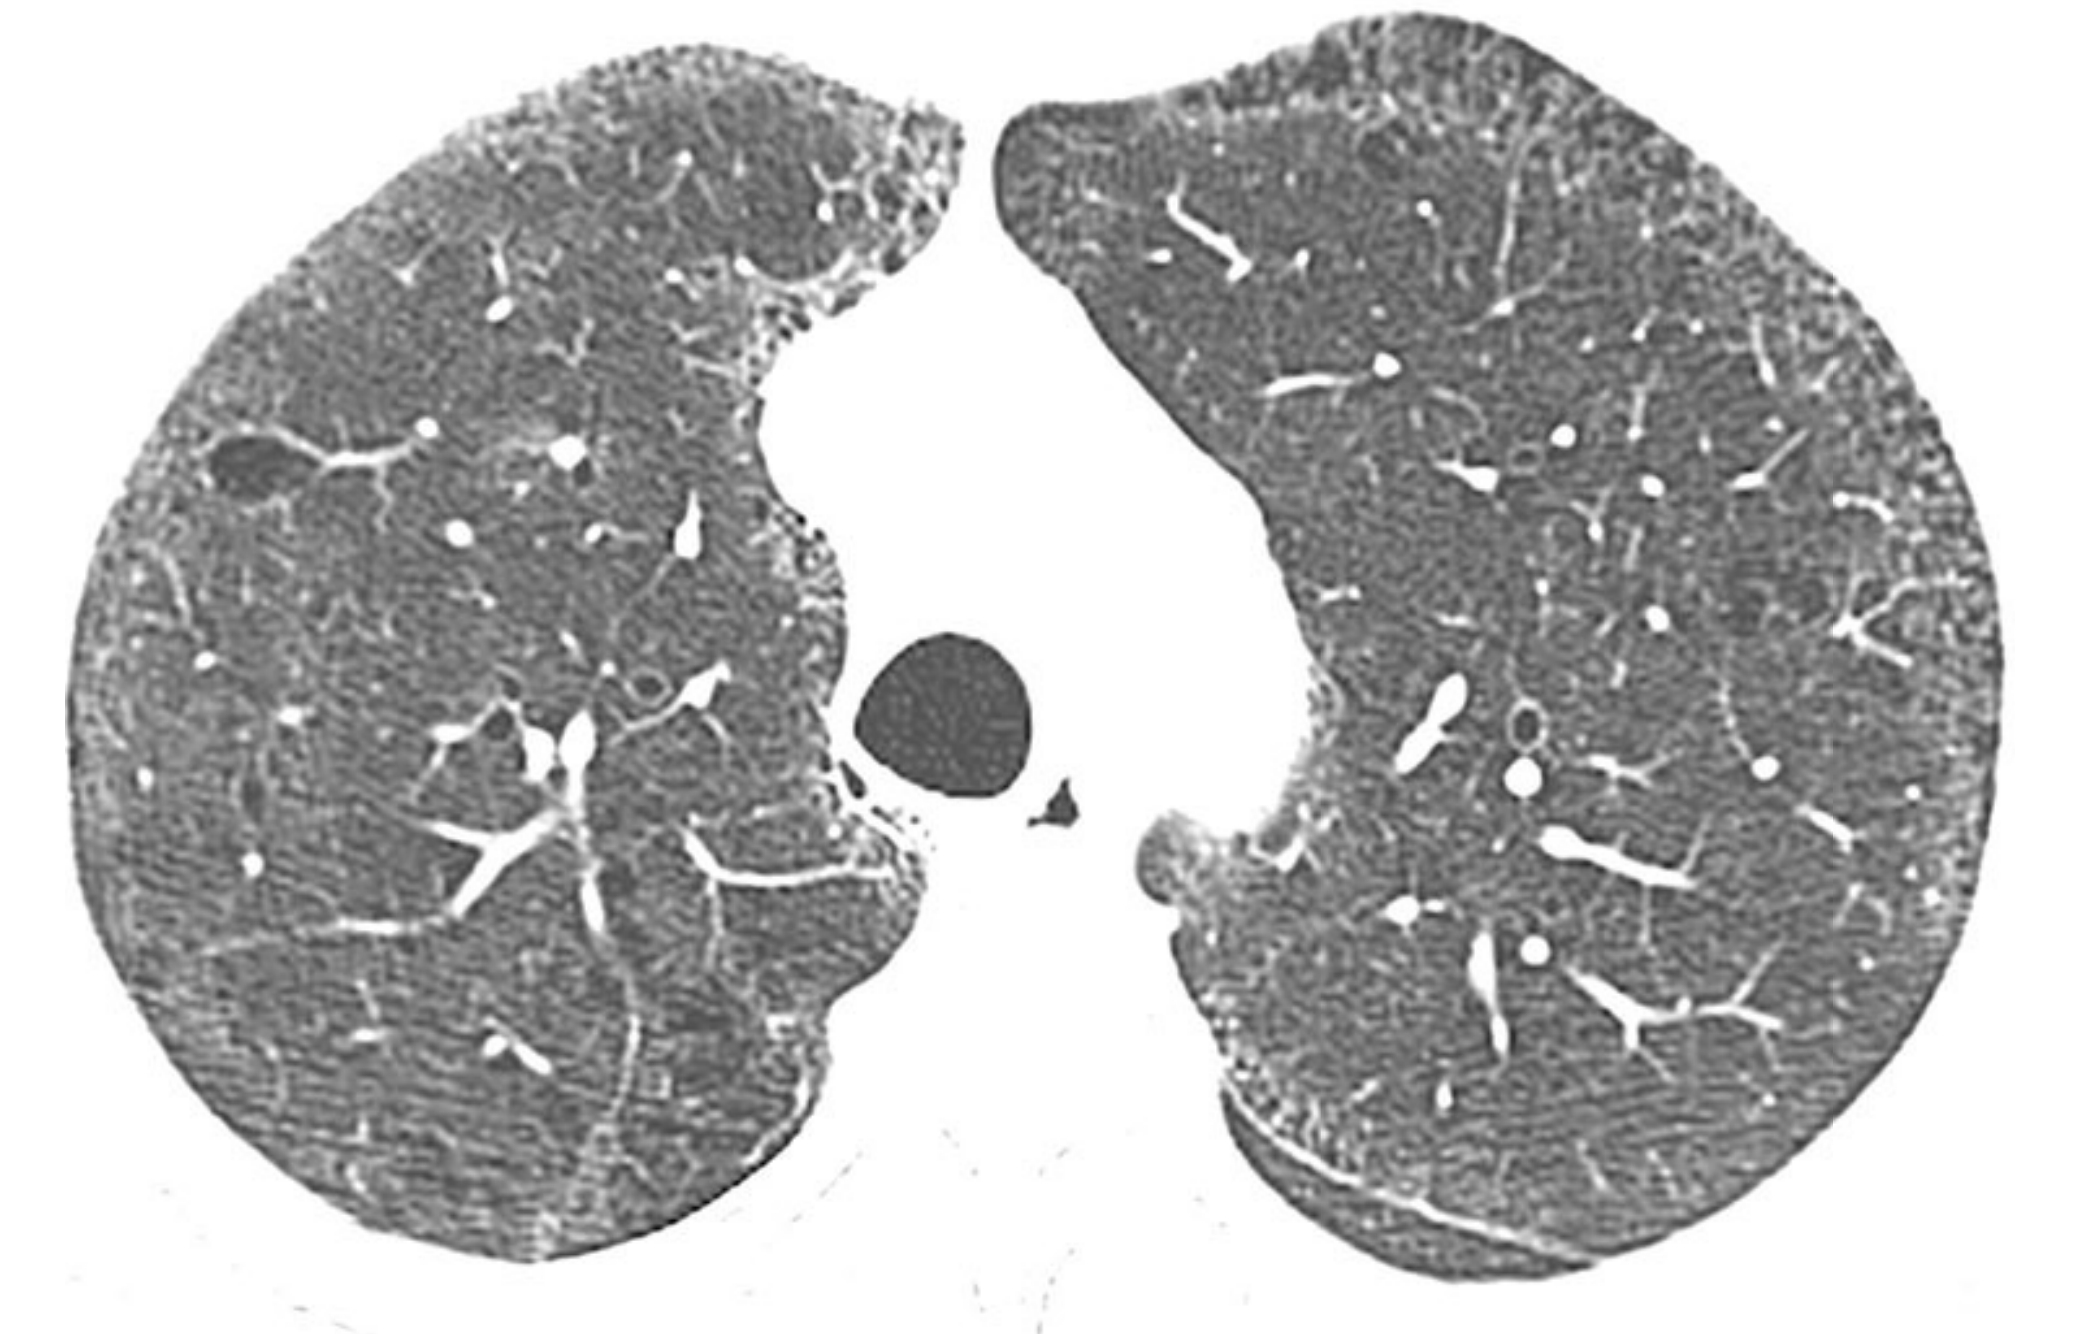

1d6b3eec372d7c316be21a0d6fbe74cc.jpg

家族性肺纤维化。

同一家族的2例家族性肺纤维化(A和B);活检证实,其组织学类型为普通型间质性肺炎(UIP)。

A. 1例患者表现为肺基底部分布为主的斑片状GGO和轻度牵拉性支气管扩张,B.另一患者表现为肺上叶和中央区分布为主的网状影、牵拉性支气管扩张和肺囊肿。家族性肺纤维化患者的HRCT表现通常不典型。